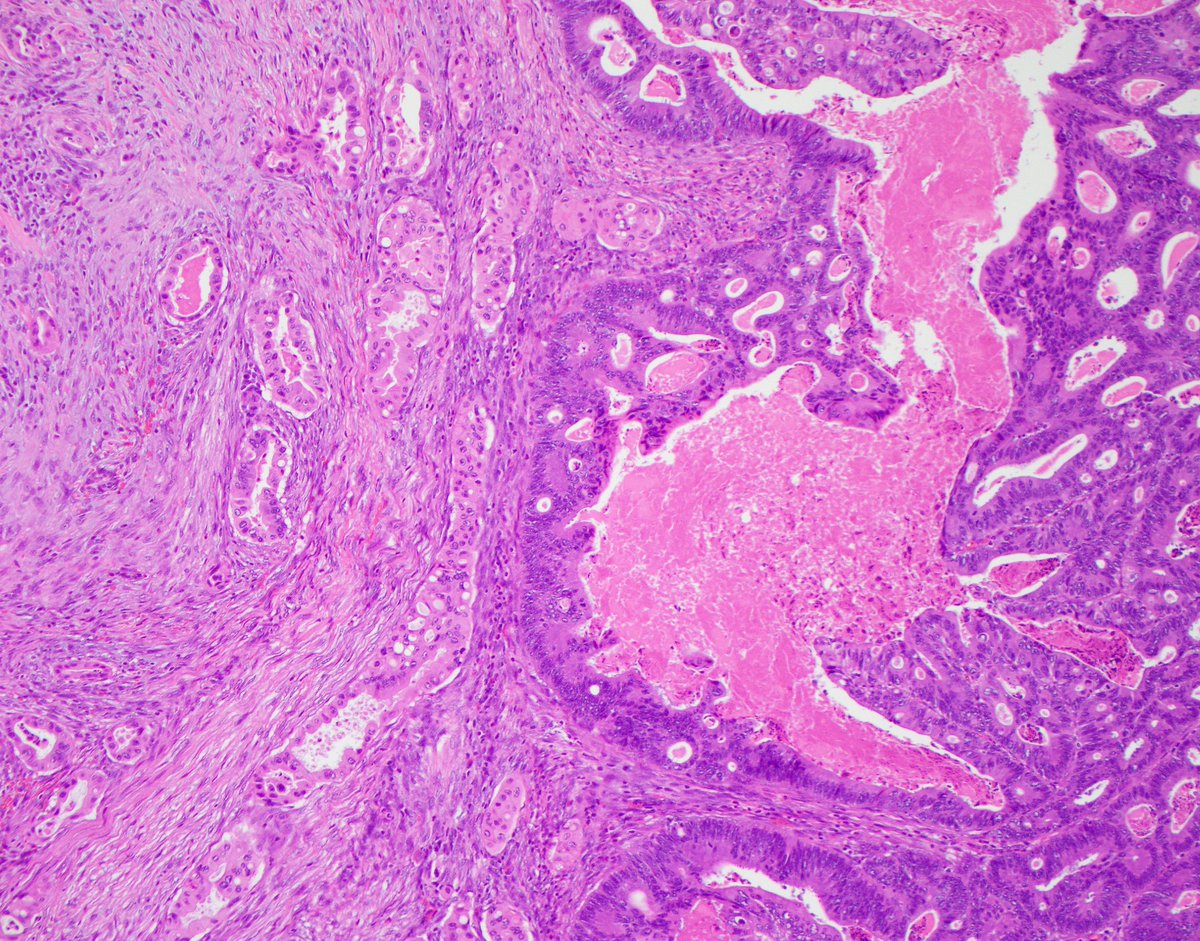

The adenocarcinoma (below) is devoid of pigment due to the paucity of macrophages within the lesion.

Thanks for all of the great participation! This is a resection specimen removed for adenocarcinoma with striking melanosis coli. The histologic correlate is below, showing numerous pigment laden macrophages within the lamina propria:

It's not ink! The pale tan polypoid area shows invasive adenocarcinoma. But why is the surrounding mucosa so dark?